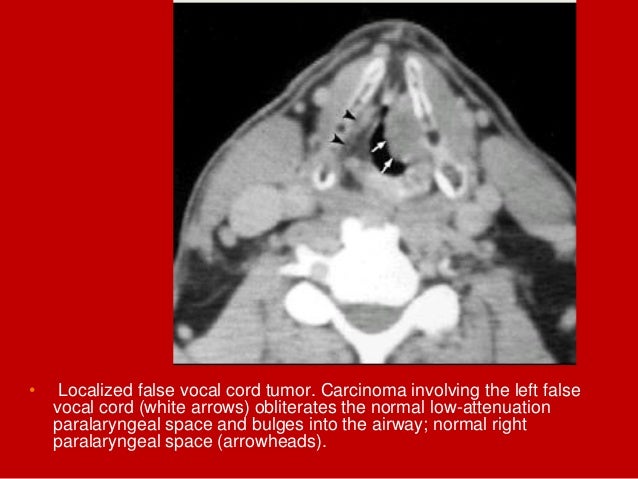

23. 23. • Localized false vocal cord tumor. Carcinoma involving the left false vocal cord (white arrows) obliterates the normal low-attenuation paralaryngeal space and bulges into the airway; normal right paralaryngeal space (arrowheads).